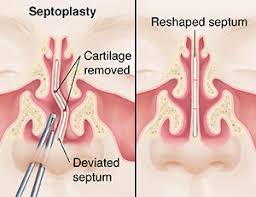

Overview

Package includes:

Days in hospital : 2 to 3 Days (For patient and one attendant)

Days in hotel : 7 Days (For patient and one attendant)

Room type in hospital : Shared

Room type in hotel : Private

Hotel category: Standard

Value added benefits of the Septoplasty: